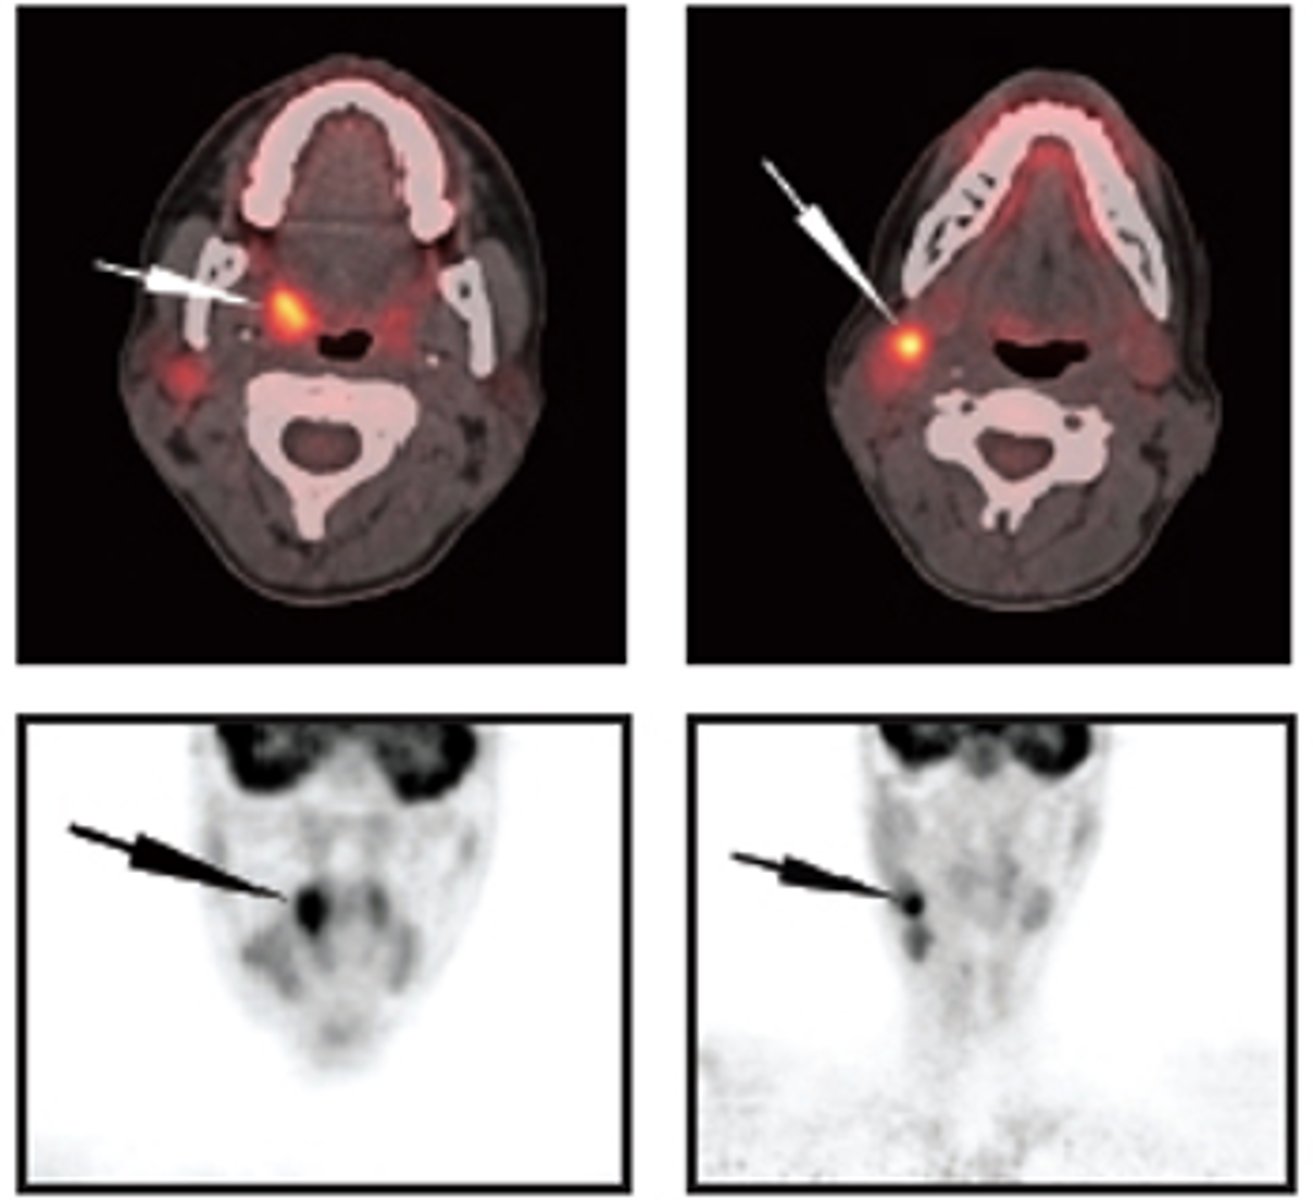

PET

ID the type of Imaging modality:

- Pano

- CT

- CBCT

- MRI

- Technetium 99 bone scans

- PET

CT

because PET scans are usually blurry, what other imaging modality is it superimposed with for identification and diagnostic purposes?